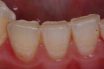

Occlusal wear

The loss of tooth structure caused by attrition or abrasion due to functional and parafunctional contact of opposing teeth. The attritional loss of substance on opposing occlusal surfaces in natural or artificial teeth; the modification of tooth cusps, ridges, and grooves by functional use.